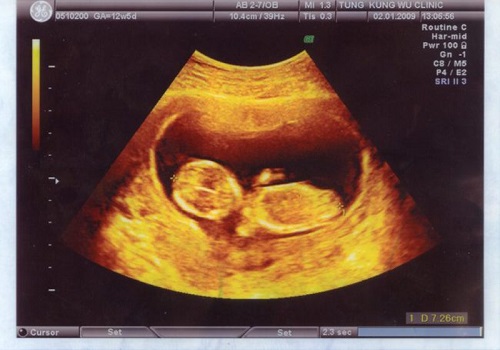

Phá thai 7 tuần hết bao nhiêu tiền? Các yếu tố quyết định đến chi phí

Phá thai 5 tuần tuổi có được không? Phương pháp an toàn

Phá thai 3 tháng tuổi có an toàn không? Lưu ý những gì

Phá thai 2 tháng tuổi có nguy hiểm không?

Đình chỉ thai bằng thuốc thực hiện cho tuổi thai nào? Ở đâu an toàn